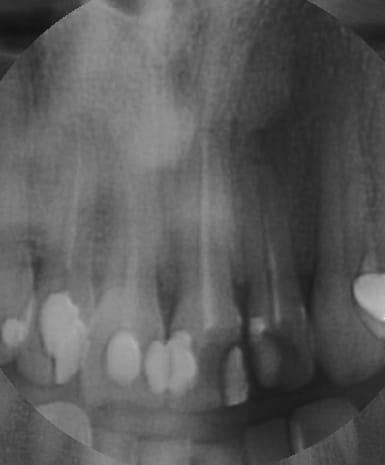

Zoom incisives eb4rim - Eugenol

Retraitement et cour prov ej8sen - Eugenol

Canaux calcifi s e685ou - Eugenol

Avec provisoires o4ho8c - Eugenol